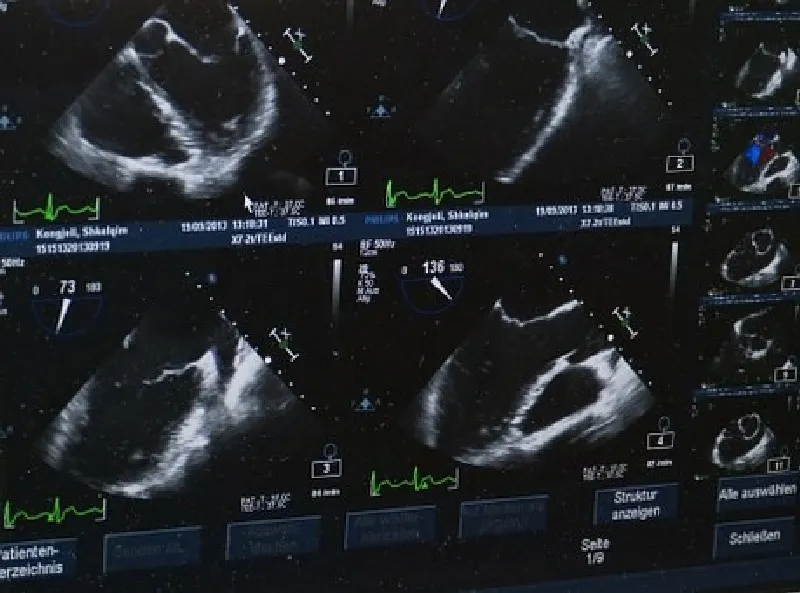

COMO ESCOLHER UMA IMPRESSORA PARA APARELHO DE ULTRASSOM

No Brasil, aproximadamente 50 mil médicos exercem a Ultrassonografia, com mais de 10 variações do exame, que pode ser recomendado a gestantes, pessoas com problemas digestivos ou até para verificar veias e artérias. Por isso, existe a preocupação de atender a essa especialidade médica com a mais adequada impressora para aparelho de ultrassom.